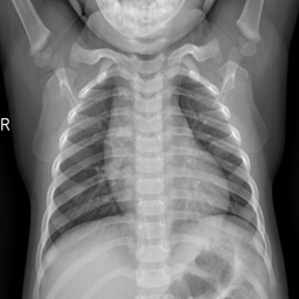

Samples of the dataset are depicted in Figure 3.

The dataset is arbitrarily partitioned among each client (). , and then the prediction performance results in the encrypted-domain are compared with the results of the plain-domain.